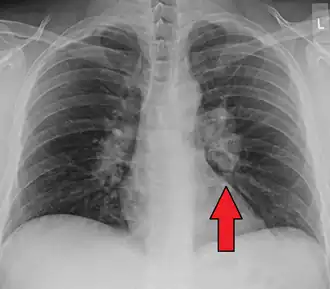

-

Hilar adenopathy especially on the person's left (AP CXR) -